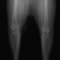

■ 症例20 ポメラニアン 8ヶ月 1.8kg

左右膝蓋骨脱臼 グレードⅢ

2ヶ月前から間欠的跛行が認められ、両膝の膝蓋骨脱臼整復術を行った。

手技は縫工筋及び内側広筋の解放、脛骨粗面の外側転位、滑車ブロック形造溝術、内外側関節包の縫縮を選択し実施した。

右側の膝蓋骨脱臼は上記手技で整復されたものの、左側はそれのみでは膝蓋骨が浮く様子が認められた。その為、PDS縫合糸にて膝蓋靱帯を1糸のみ縫合し、靱帯の縫縮を行った。

膝蓋骨脱臼は膝関節における膝蓋骨の内外側の脱臼と定義されるが、時として単純な内外の脱臼ではなく、膝蓋骨が大きく前方に浮き上がるように脱臼する場合がある。特にトイプードルやポメラニアンといった犬種に多く認められる。

内側脱臼に加えて前方への浮き上がりを矯正する為に、従来より脛骨粗面転移により膝蓋靭帯を外方と下方に引っ張り、固定する方法を選択する。膝蓋骨の前方への浮き上がりが軽度の場合は、従来法ではなく関節包の縫縮で対応していた。しかし、一部の症例で膝蓋骨の動きが悪くなり伸展機構が円滑に機能せずロボット様歩行になるケースがあった。

その為、膝蓋靭帯自体を縫縮する方法を採用した。この方法により、膝関節の伸展機構を妨げず膝蓋骨の軽度の浮きを矯正することが可能となった。

本症例の経過は良好である